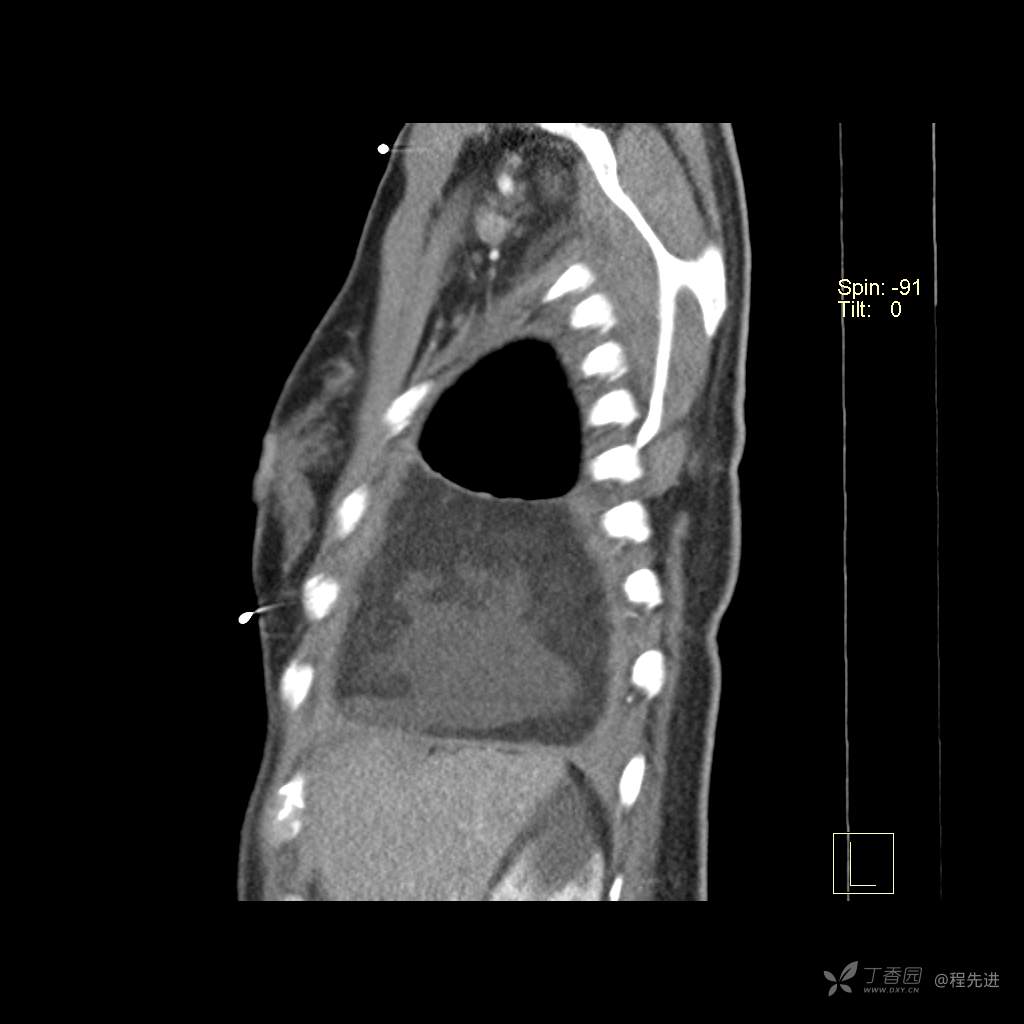

患者性别:女

患者年龄:51岁

简要病史:胸闷半年